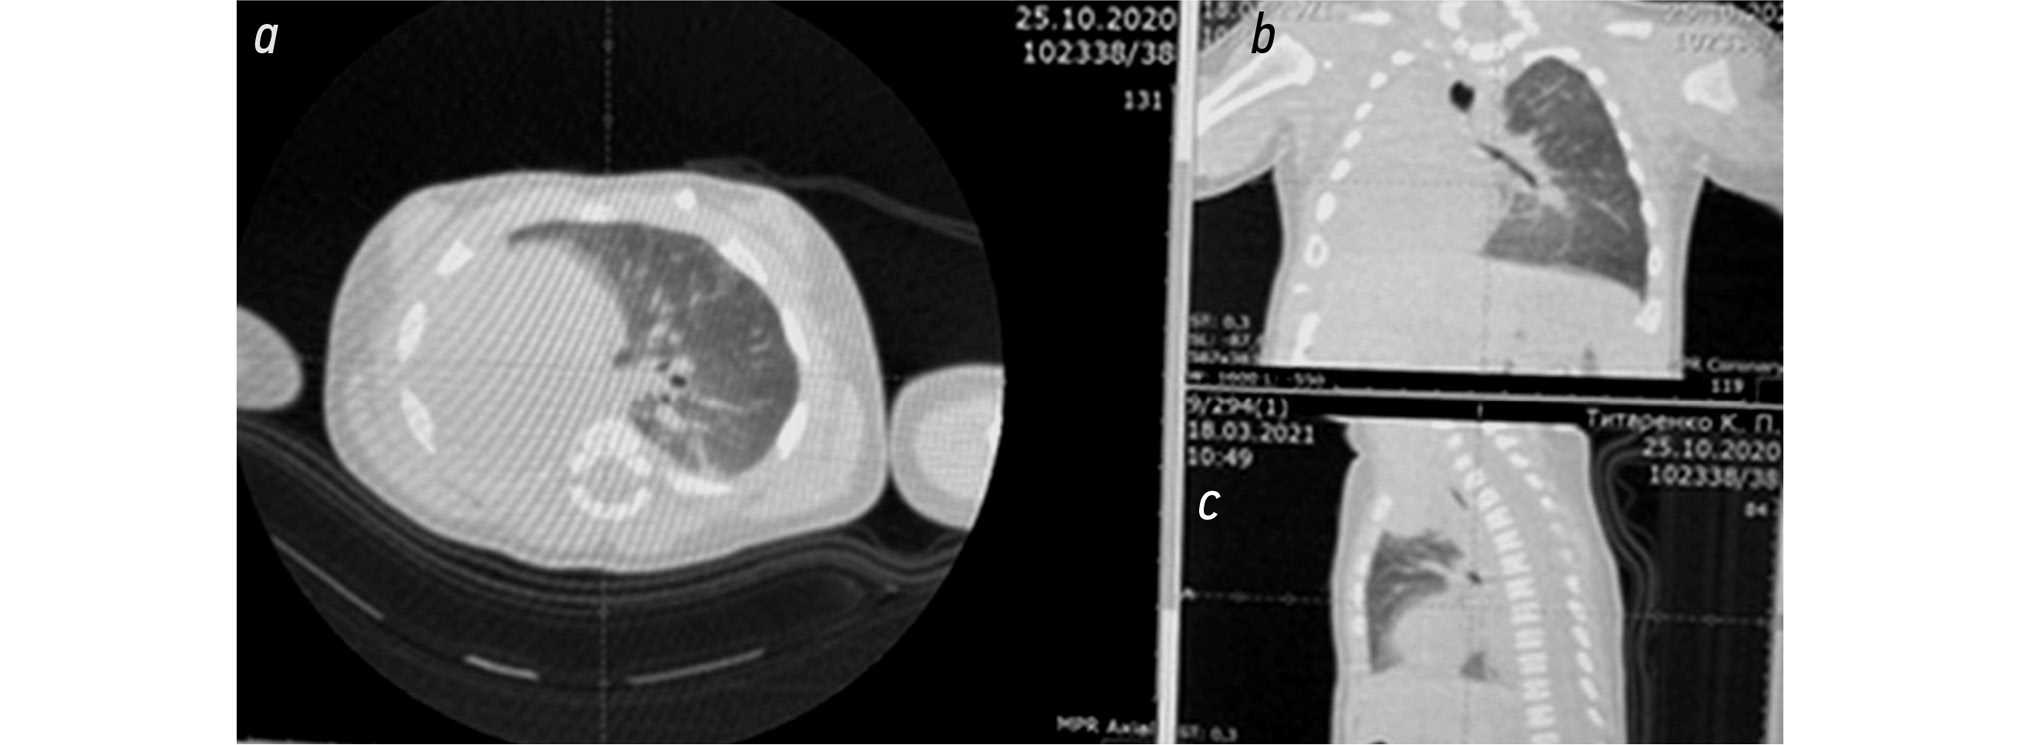

По данным МСКТА органов грудной полости, выполненной в возрасте 1 г. 2 мес., определяется картина гипоплазии с умеренными фиброзными изменениями паренхимы правого лёгкого, в также умеренное компенсаторное вздутие левого лёгкого с дислокацией органов средостения вправо. В сегментарных и субсегментарных бронхах верхней и средней доли правого лёгкого обнаружены единичные цилиндрические бронхоэктазы (рис. 9, рис. 10).

Рис. 9. Мультиспиральная компьютерная томография- ангиография органов грудной полости в возрасте 1 г. 2 мес.

Fig. 9. Multispiral computed tomography-angiography of the thoracic cavity at the age of 1 year 2 months.

Рис. 10. Мультиспиральная компьютерная томография- ангиография органов грудной полости в возрасте 1 г. 2 мес.

Fig. 10. Multispiral computed tomography-angiography of the thoracic cavity at the age of 1 year 2 months.